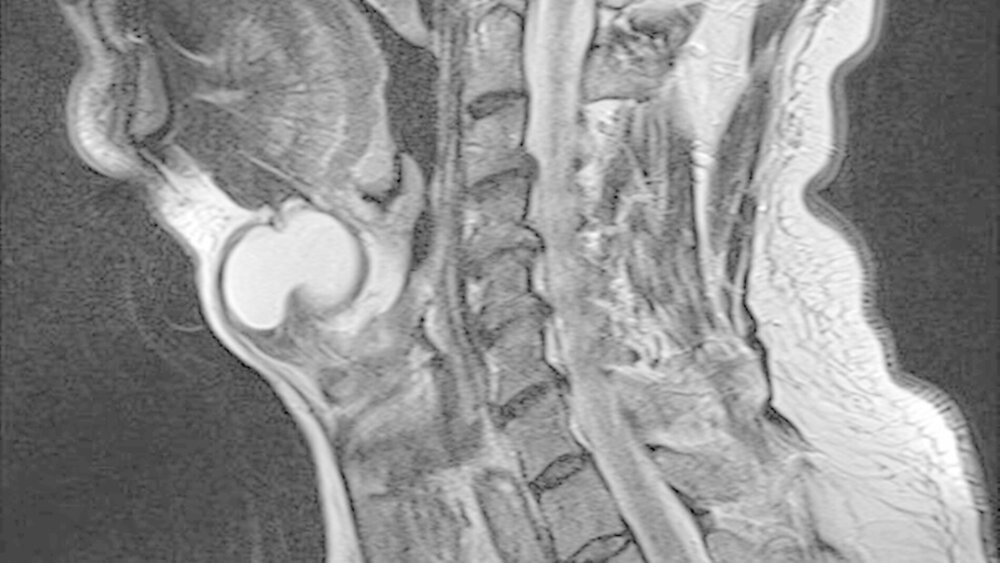

Die unter ambulanten Bedingungen angefertigte schnittbildgebende MRT-Untersuchung des Halses zeigte eine 41x35x27 mm große, gut abgrenzbare, und abgekapselte Raumforderung mit homogener Binnenstruktur. Die Dichtewertemessung wies anhand der Verteilung der Hounsfield-Einheiten einen mit flüssigkeits-äquivalentem, gefüllten Hohlraum auf (Abbildung 2a). Dieser war mit einer mittigen Einschnürung in der Medianebene des Halses und in der Mitte des Os hyoideum lokalisiert (Abbildung 2b). Dabei wird die Verdrängung des aerodigistiven, benachbarten Raumes sowie die Anhebung des Mundbodens und der Zungengrundmuskulatur deutlich (Abbildung 2c).